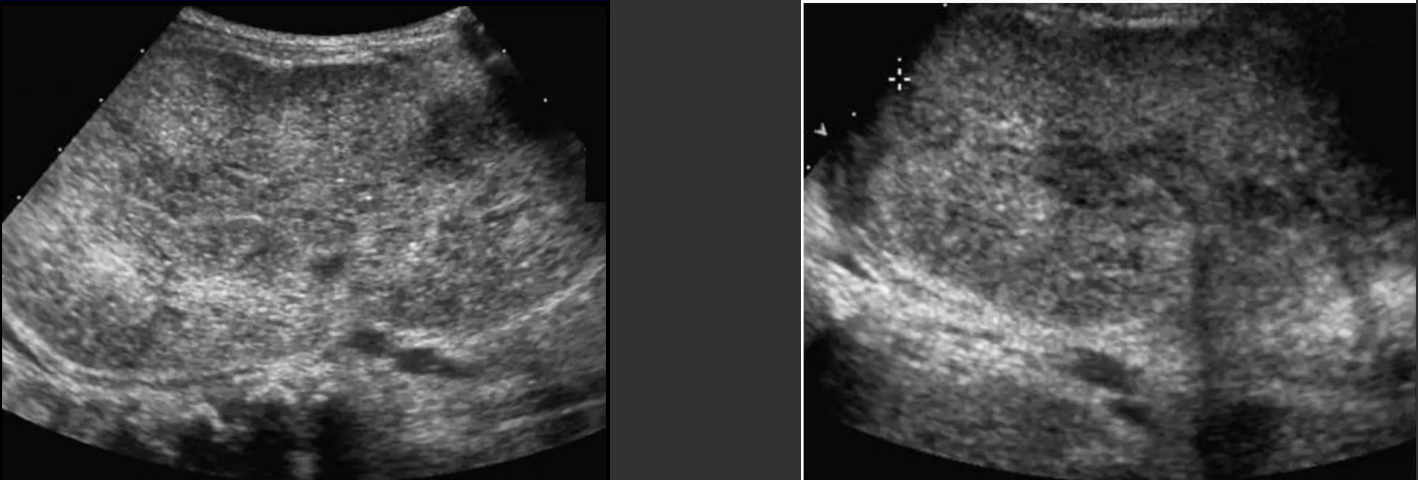

Fatty Infiltration/Fatty Liver Disease → excess fat builds up in liver cells

clinical hx: DM, older male, EtoH abuse, obesity

s/sx: asymptomatic, elevated LFTs, palpable liver

2D US: enlarged liver, diffusely echogenic parenchyma, mild → slightly brighter, can still see periportal fat in veins, moderate → increased echoes, slight impaired diaphragm & vessel borders, severe → significantly brighter, less penetration of posterior right lobe, poor visualization of diaphragm & vessels

DDX: hepatitis (echogenic liver, hepatomegaly, but has bright portal veins), cirrhosis (increased echogenicity, but coarse and nodular)